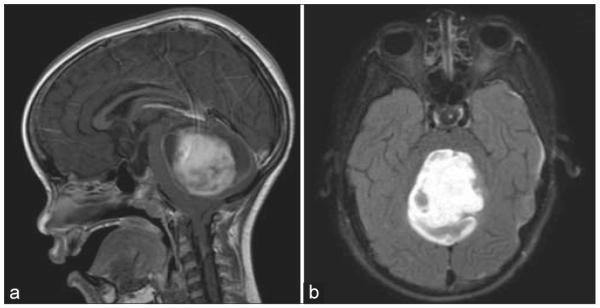

Materials and methods: Utilizing specimens from cases of pilocytic astrocytoma (n = 5), medulloblastoma (n = 5), and low-grade diffuse astrocytoma (n = 1), immunofluorescence were performed using primary antibodies against CD31, glial fibrillary acidic protein (GFAP), and aquaporin 4 (AQ4). Clinical, magnetic resonance imaging, operative, and histopathological findings were analyzed.

Results: Strongly-enhancing areas of medulloblastoma exhibited complete BBB breakdown with sparse GFAP and AQ4 staining around CD31-positive vessels. Moderately enhancing regions of pilocytic astrocytomas exhibited regions of intact BBB and vasculature surrounded by dense GFAP staining but reduced and disorganized AQ4 staining, suggesting tumor cells could not fulfill physiological BBB support. Non-enhancing low-grade diffuse astrocytoma demonstrated intact BBB with intense peri-microvasculature GFAP and AQ4 staining. AQ4 stained so strongly that AQ4 visualization alone delineated CD31-positive vessels.